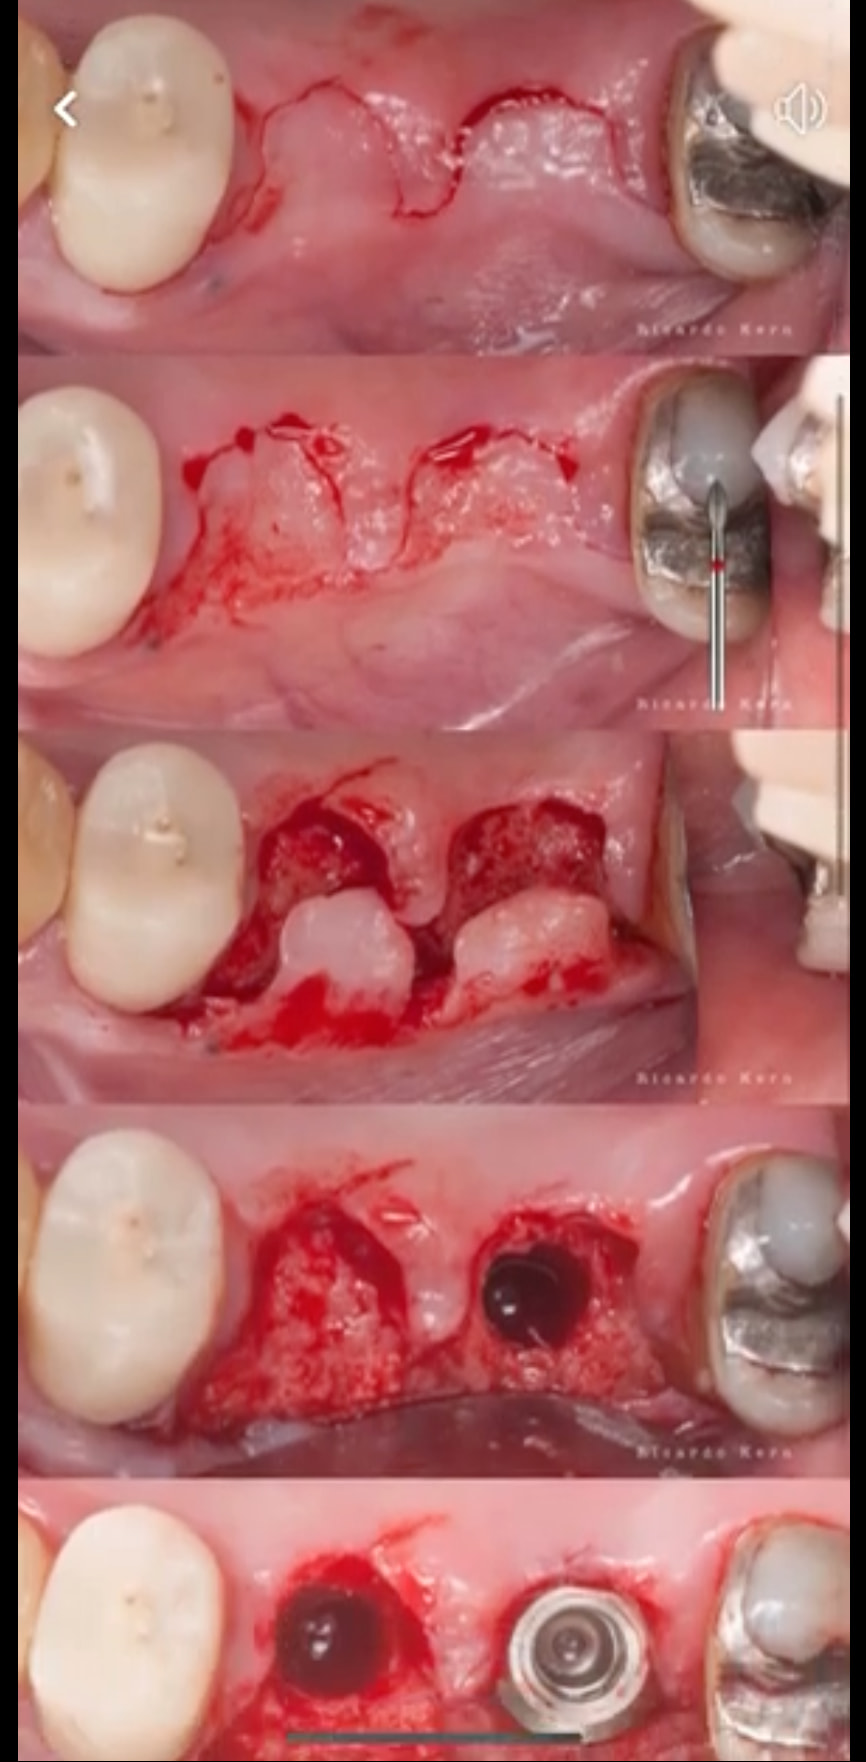

This case involves the Immediate implant placement of implants in #12 and #13 (recurrent caries) followed by a modified palatal roll for buccal contour augmentation. The case highlights an aspect of implant dentistry that often gets overlooked, namely the restoration of the buccal contour. The modified roll technique shown in this video was described by Tarnow and Scharf (Int J Periodontics Restorative Dent . 1992;12(5):415-25) and involves a partial thickness flap on the palatal, separation of the connective tissue from the palatal while still maintaining it’s attachment to the buccal tissue, and finally tucking of the pedicle beneath the buccal tissue to augment the soft tissue. All of the steps detailed above are covered in the video, as well as the post-op photographs showing the final results and restoration.

not sure if I can still reply this post, just wonder have you considered using S rolled flap with de-epithelialization to uncover implants instead of using palatal pedicle CTG? just like the attached picture, as shown below, blue area is the area of de-epitheliazation before tug around implant healing abutment. like Richard kern’s lecture ?

( Richard kern’s lecture )